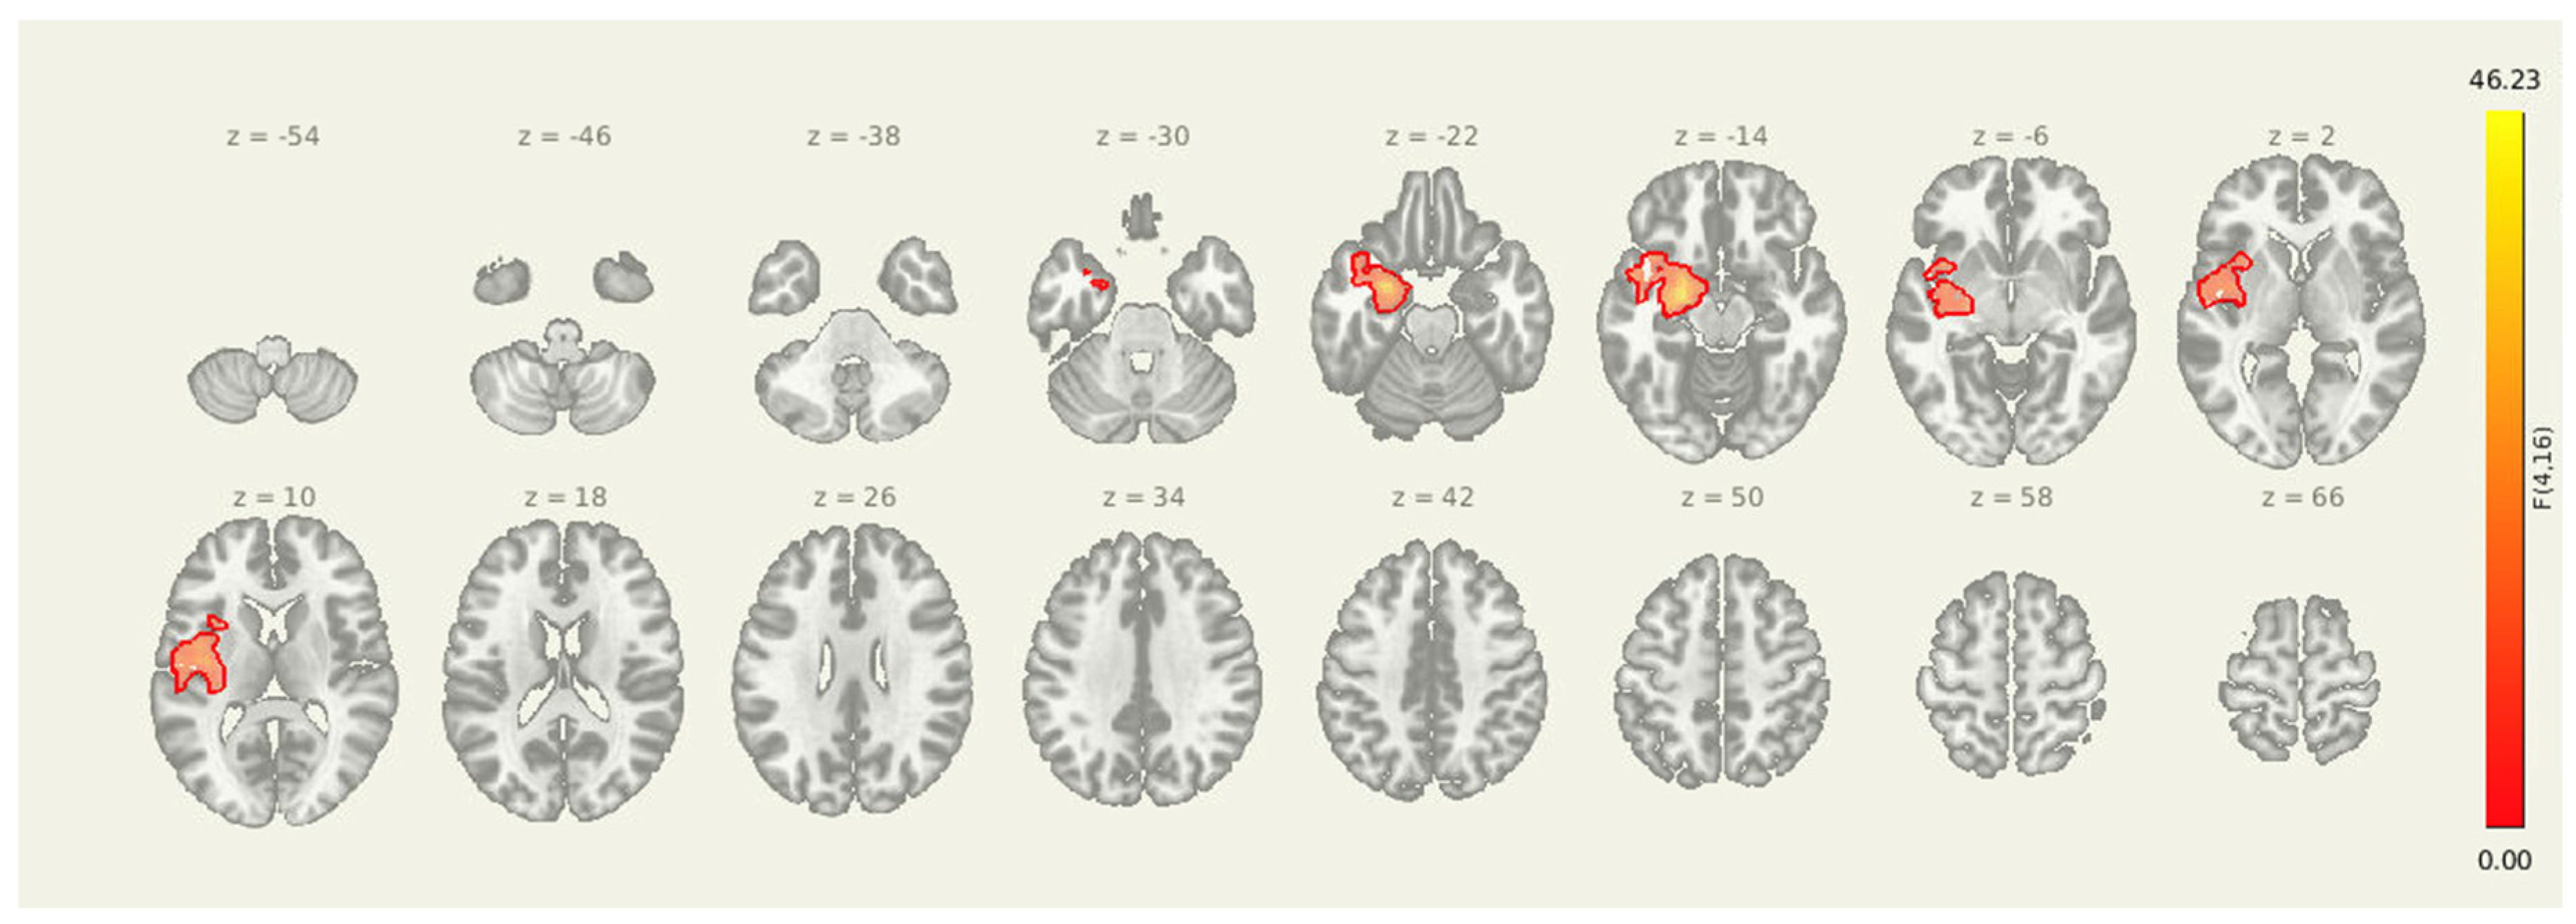

Insula Seed PRE>POST

For the insula seed, pre-intervention connectivity was significantly greater than post-intervention in multiple regions: the left inferior frontal gyrus (MNI: -48, +12, -02; cluster size = 266 voxels; p-FDR < 0.001), the right inferior frontal gyrus (+48, +10, +00; 256 voxels; p-FDR < 0.001), and the left ventral striatum/putamen (-28, +02, +08; 65 voxels; p-FDR < 0.001). These regions are commonly involved in emotional processing, interoceptive integration, and motor preparation, and the observed reductions in connectivity suggest decreased insula-driven engagement of salience and affective-motor circuits following the intervention.

Table 5. Post-intervention reductions in connectivity from the insula seed to frontal and striatal regions. All clusters reported here were significant at p-FDR < 0.001.

66. Cluster (MNI x, y, z) 67. Size (voxels) 68. p-FWE 69. p-FDR 70. Location

71. -48, +12, -02 72. 266 73. < 0.001 74. < 0.001 75. Left Inferior Frontal Gyrus

76. +48, +10, +00 77. 256 78. < 0.001 79. < 0.001 80. Right Inferior Frontal Gyrus

81. -28, +02, +08 82. 65 83. < 0.001 84. < 0.001 85. Left Ventral Striatum / Putamen

Amygdala-Insula-Thalamus Seed

Figure 4. Post-intervention reductions in connectivity from limbic seed regions. Significant decreases in seed-to-voxel connectivity were observed from the amygdala, insula, and thalamus following the intervention. Clusters included sensorimotor, frontal, and subcortical regions. Results are thresholded at p-FDR < 0.05.

Table 6. Post-intervention reductions in connectivity from the amygdala-insula-thalamus seed. The cluster identified reflects decreased coupling between the amygdala and the right superior frontal gyrus.

86. Cluster (MNI x, y, z) 87. Size (voxels) 88. p-FWE 89. p-FDR 90. Location

91. +20, +18, +56 92. 133 93. 0.009064 94. 0.006499 95. Right Superior Frontal Gyrus

Seeding from amygdala-insula-thalamus Seed-to-voxel analyses revealed a significant post-intervention reduction in connectivity from the insula, amygdala, and thalamus to a cluster in the right superior frontal cortex (MNI coordinates: +20, +18, +56; cluster size = 133 voxels; p-FDR = 0.0065). These results suggest that improved prefrontal oversight may be a key mechanism through which the intervention alters pain-related brain dynamics in individuals with post-stroke headache.